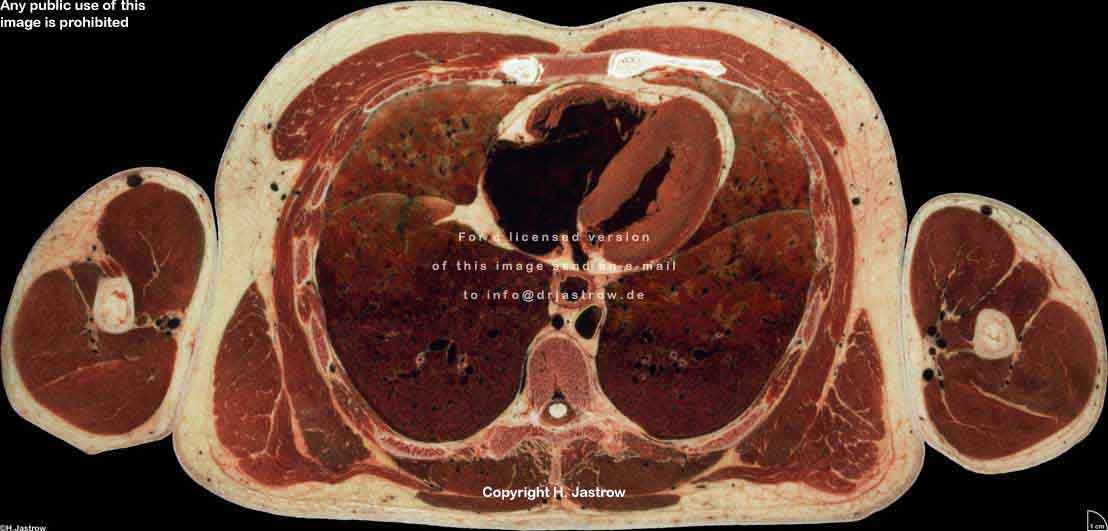

Visible Human male: Sectio transversalis 1454